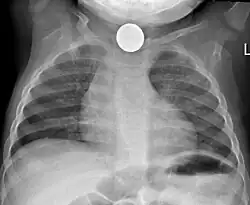

-

Foreign body aspiration with bronchoscopy finding a nut in the right bronchus. Note right lung (left of image) is hyperinflated (darker).[33] -